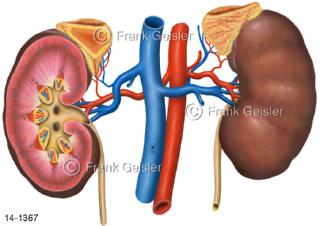

Bildergalerie Urogenitalsystem

Bilder zum Urogenitalsystem mit Urogenitalorgane, Urogenitaltrakt, zum Harn- und Geschlechtsapparat, Harnorgane und Geschlechtsorgane, Organe der Harnwege und der Fortpflanzung, Harnorgane und Geschlechtsorgane im männlichen und weiblichen Urogenitalsystem